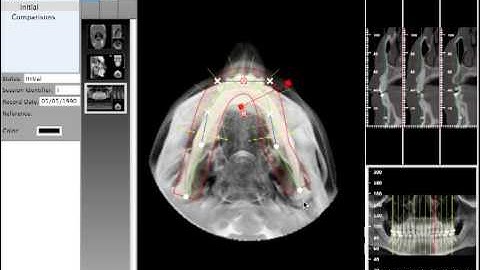

Quick Ceph Studio - Extracing Condyle Views from CT Scan